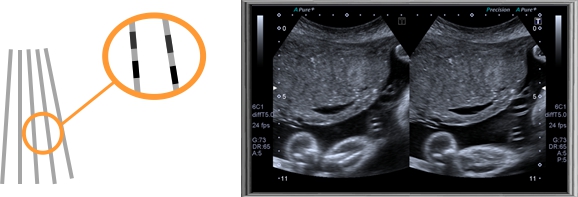

精確三維(3D)成像系統(tǒng)

全數(shù)字精確三維(3D)成像系統(tǒng),采用探頭陣元切割掃描,采集大量

精確地三維數(shù)據(jù),快速生產(chǎn)高分辨率、高清晰度的精確三維圖像,更

好的進一步測量和診斷。